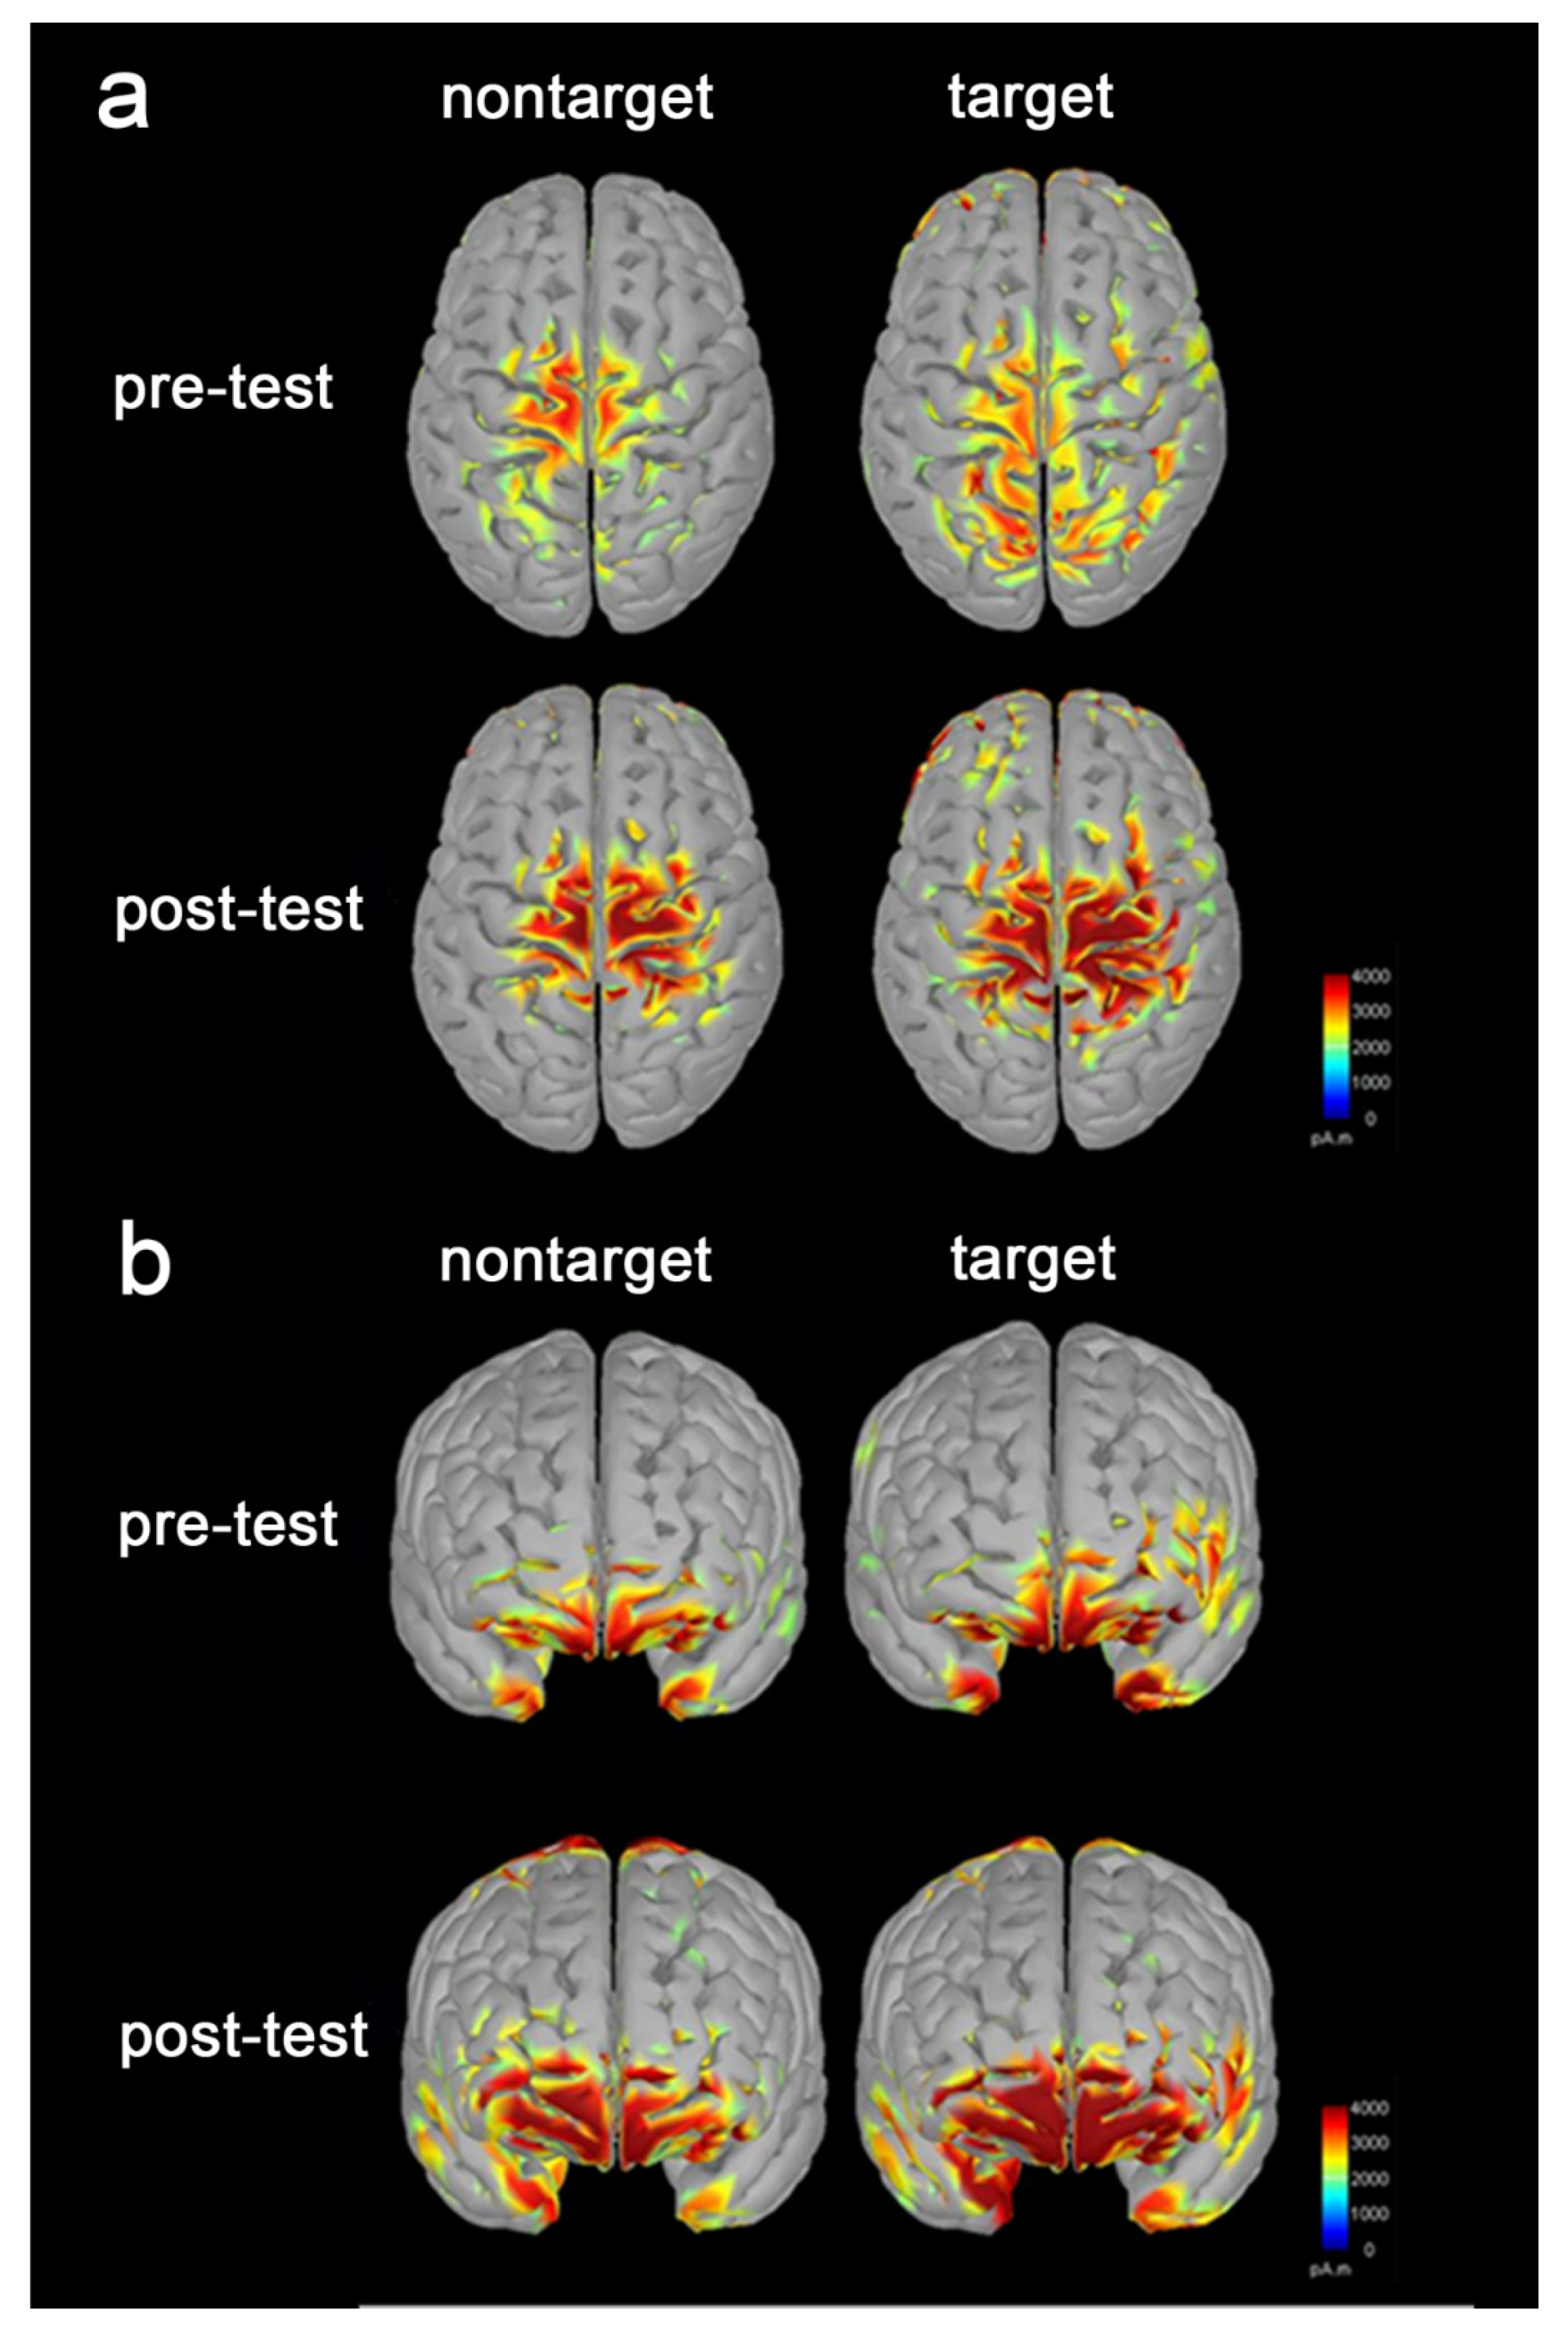

3.3. Increased Brain Activation following the Tactile Training